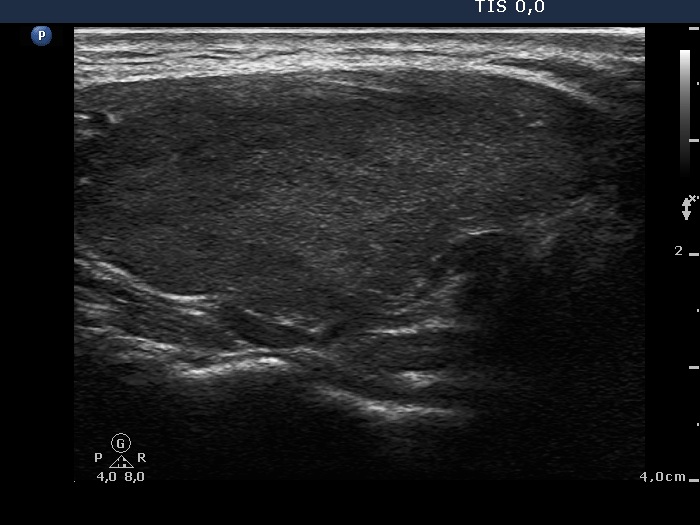

Ultrasonography. The thyroid was minimally hypoechogenic and had several more hypoechogenic areas. One of the latter located in the ventral part of the right lobe had blurred borders and an ambiguous echogenic figure. The vascularization of the thyroid was extremely increased.